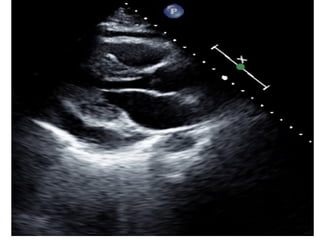

This document contains an ECG test with multiple questions and answers. It discusses cases of: 1. A 60-year-old patient with diabetes, hypertension and chest pain, showing an anterior STEMI with inferior ischemia. 2. A 55-year-old woman with shortness of breath and fatigue, showing a low-voltage ECG and echocardiogram revealing pericardial effusion due to severe hypothyroidism. 3. A 60-year-old with chest pain, showing an anteroseptal STEMI with diffuse ischemia.